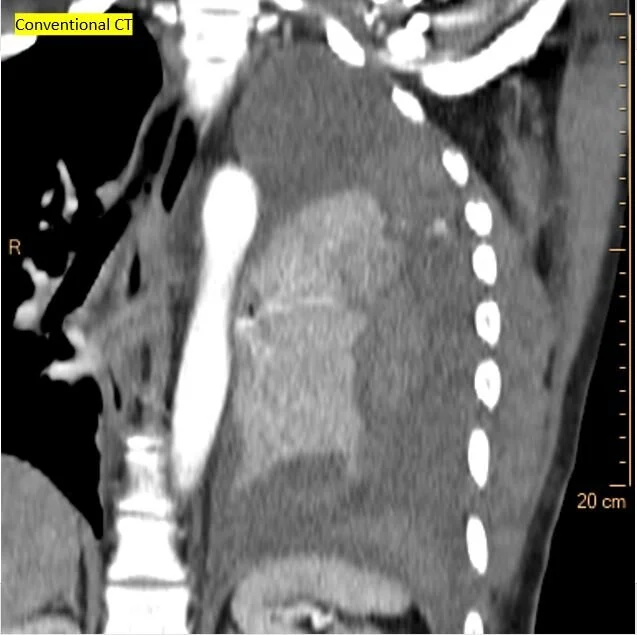

Conventional CT shows pleural thickening